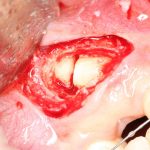

Удаление зуба, спровоцировавшего перикоронит. Наиболее вероятная в твоем случае тактика лечения

Так вот,

— если зуб, спровоцировавший перикоронит — это зуб мудрости, третий моляр или восьмерка.

— если подобное состояние у тебя не впервые, и ранее ты уже прибегал к «иссечению» десневого капюшона», да еще неоднократно.

— если по данным рентгенологической диагностики причинный зуб имеет сформированную корневую систему, зуб явно уже не прорезывается или, что хуже — упирается коронковой частью в наружную косую линию, соседний зуб или куда-нибудь еще

— если врач-ортодонт после обследования говорит, что в твоем зубном ряду нет места для восьмерок, да еще настоятельно рекомендует тебе исправление прикуса

— если ты старше 20 лет

— если из-за слабо развитой мелкой моторики, выраженного рвотного рефлекса, да и просто из-за лени ты не можешь нормально ухаживать за дальними участками зубных рядов

— если на видимой части зуба уже есть кариозная полость

— если на соседнем зубе (семерке) есть кариозная полость

— если ты не хочешь возвращаться к этой проблеме через некоторое время,

К слову сказать, что иссечение десневого капюшона над зубом мудрости, что само удаление зуба мудрости занимают одно и то же время, постоперационная симптоматика, назначения и рекомендации практически идентичны, но в одном случае ты, фактически, оставляешь в зубном ряду мину замедленного действия, во втором — кардинально и бескомпромиссно, как и положено нормальному здравомыслящему человеку, решаешь проблему раз и навсегда.